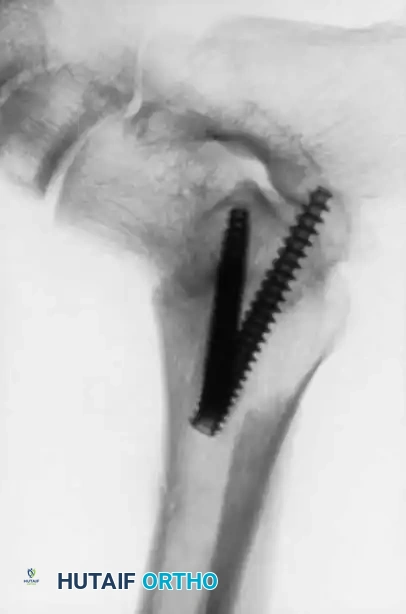

Image

Advanced hemophilic arthropathy of the ankle often requires aggressive intervention. When arthroscopic synovectomy fails to control symptoms in end-stage disease, definitive stabilization via ankle arthrodesis utilizing rigid internal fixation becomes necessary to eliminate pain and prevent further hemorrhagic episodes.